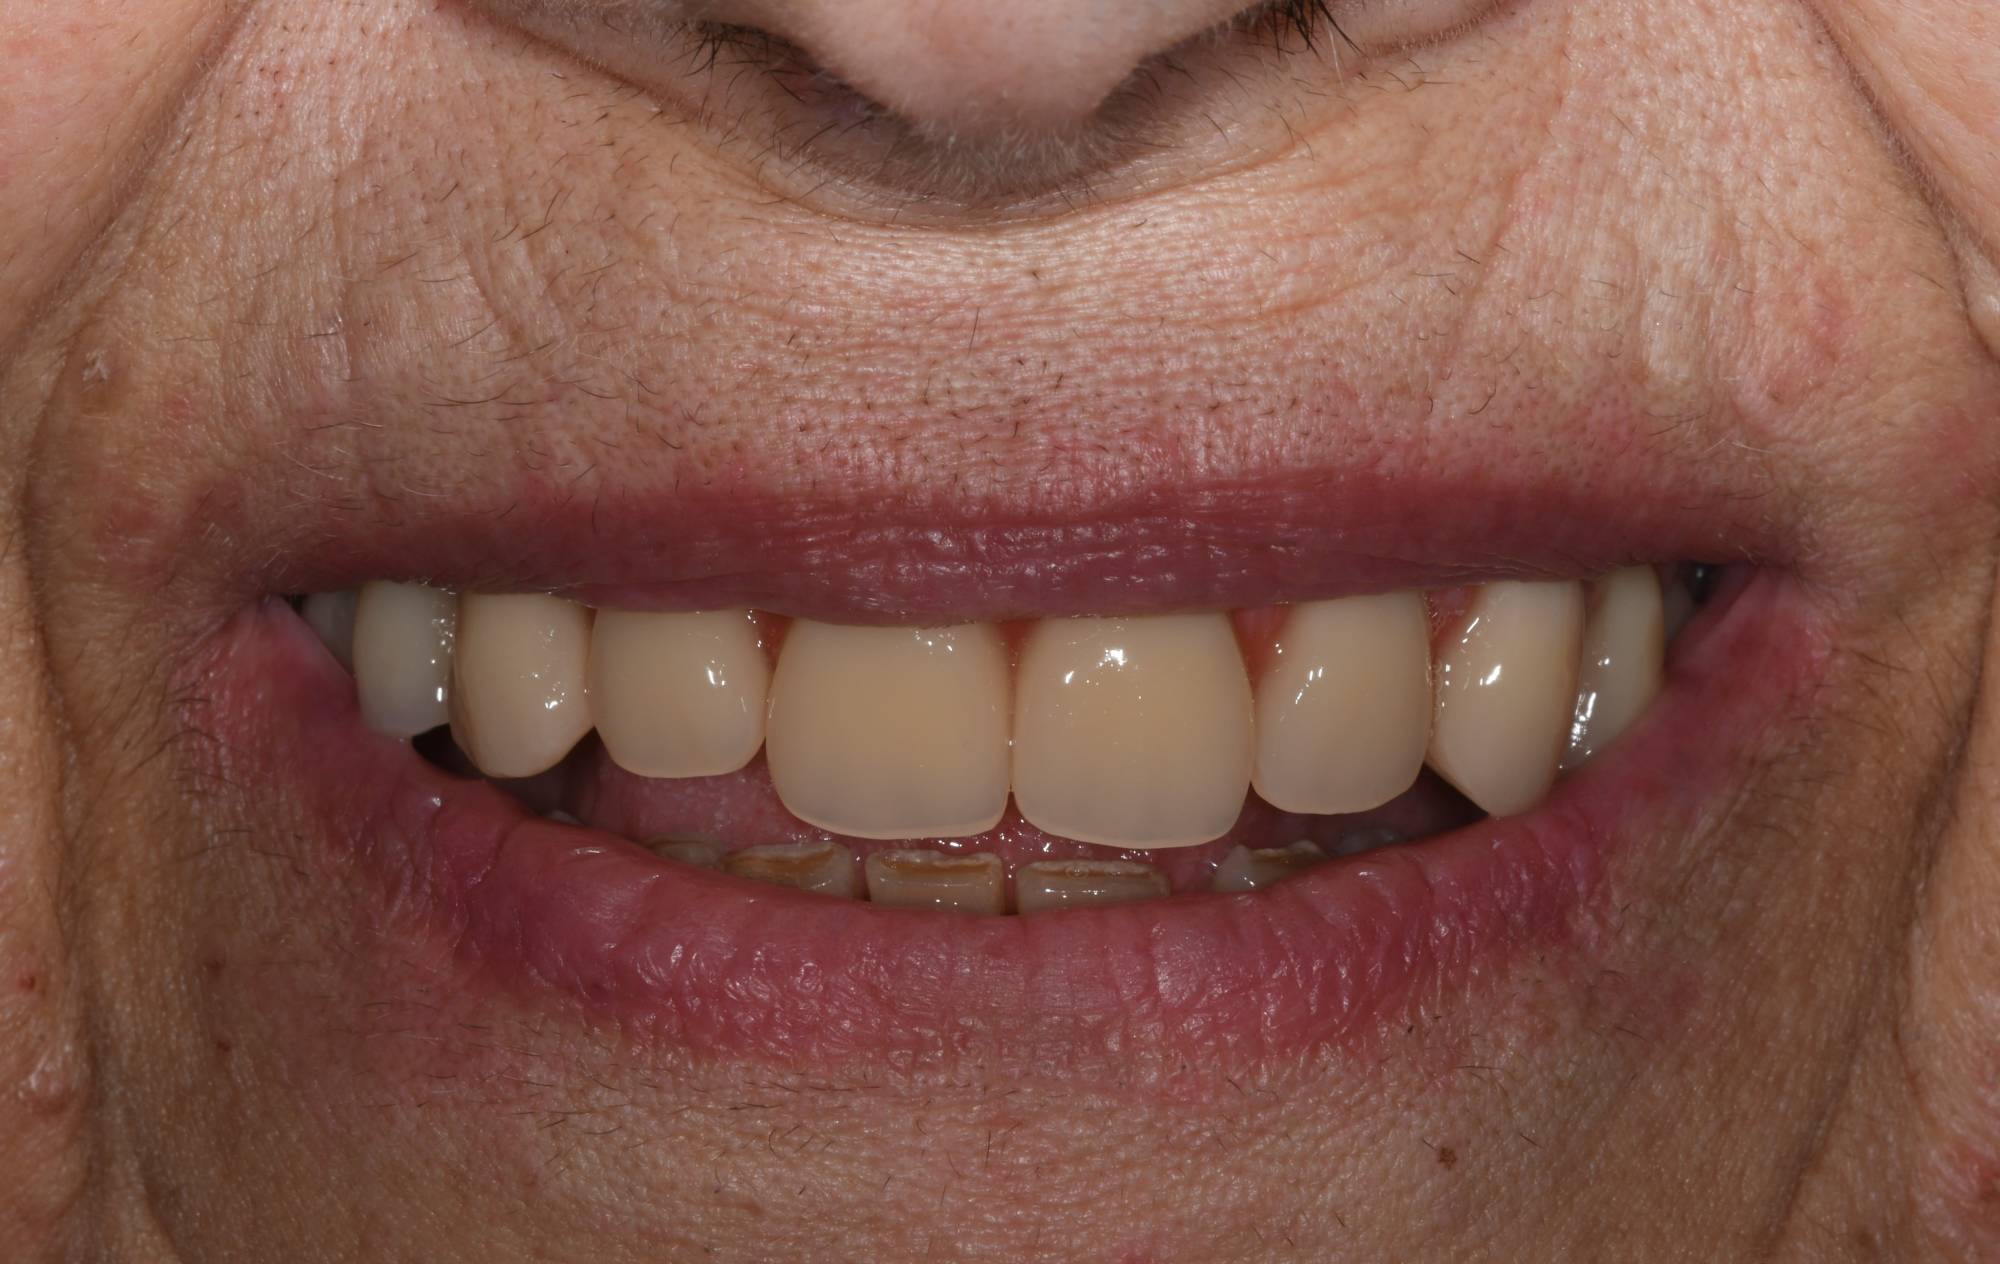

L'impianto dentale osteointegrato è una sorta di radice artificiale che si inserisce nell’osso del paziente, per rimpiazzare un dente mancante.

L'impianto, oltre a essere un metodo sicuro, garantisce l'aspetto esteriore e la piena funzionalità di un dente naturale. Oltre a ciò, mantiene l’integrità dell’osso, non va ad intaccare i denti adiacenti - come invece farebbe un ponte - e migliora l’estetica facciale prevenendo la perdita ossea.

Gli impianti sono molto versatili e possono essere usati per sostituire un dente singolo, più denti fissi o addirittura un'intera arcata. Inoltre, possono essere inseriti sotto una protesi mobile per stabilizzarla migliorandone il comfort.